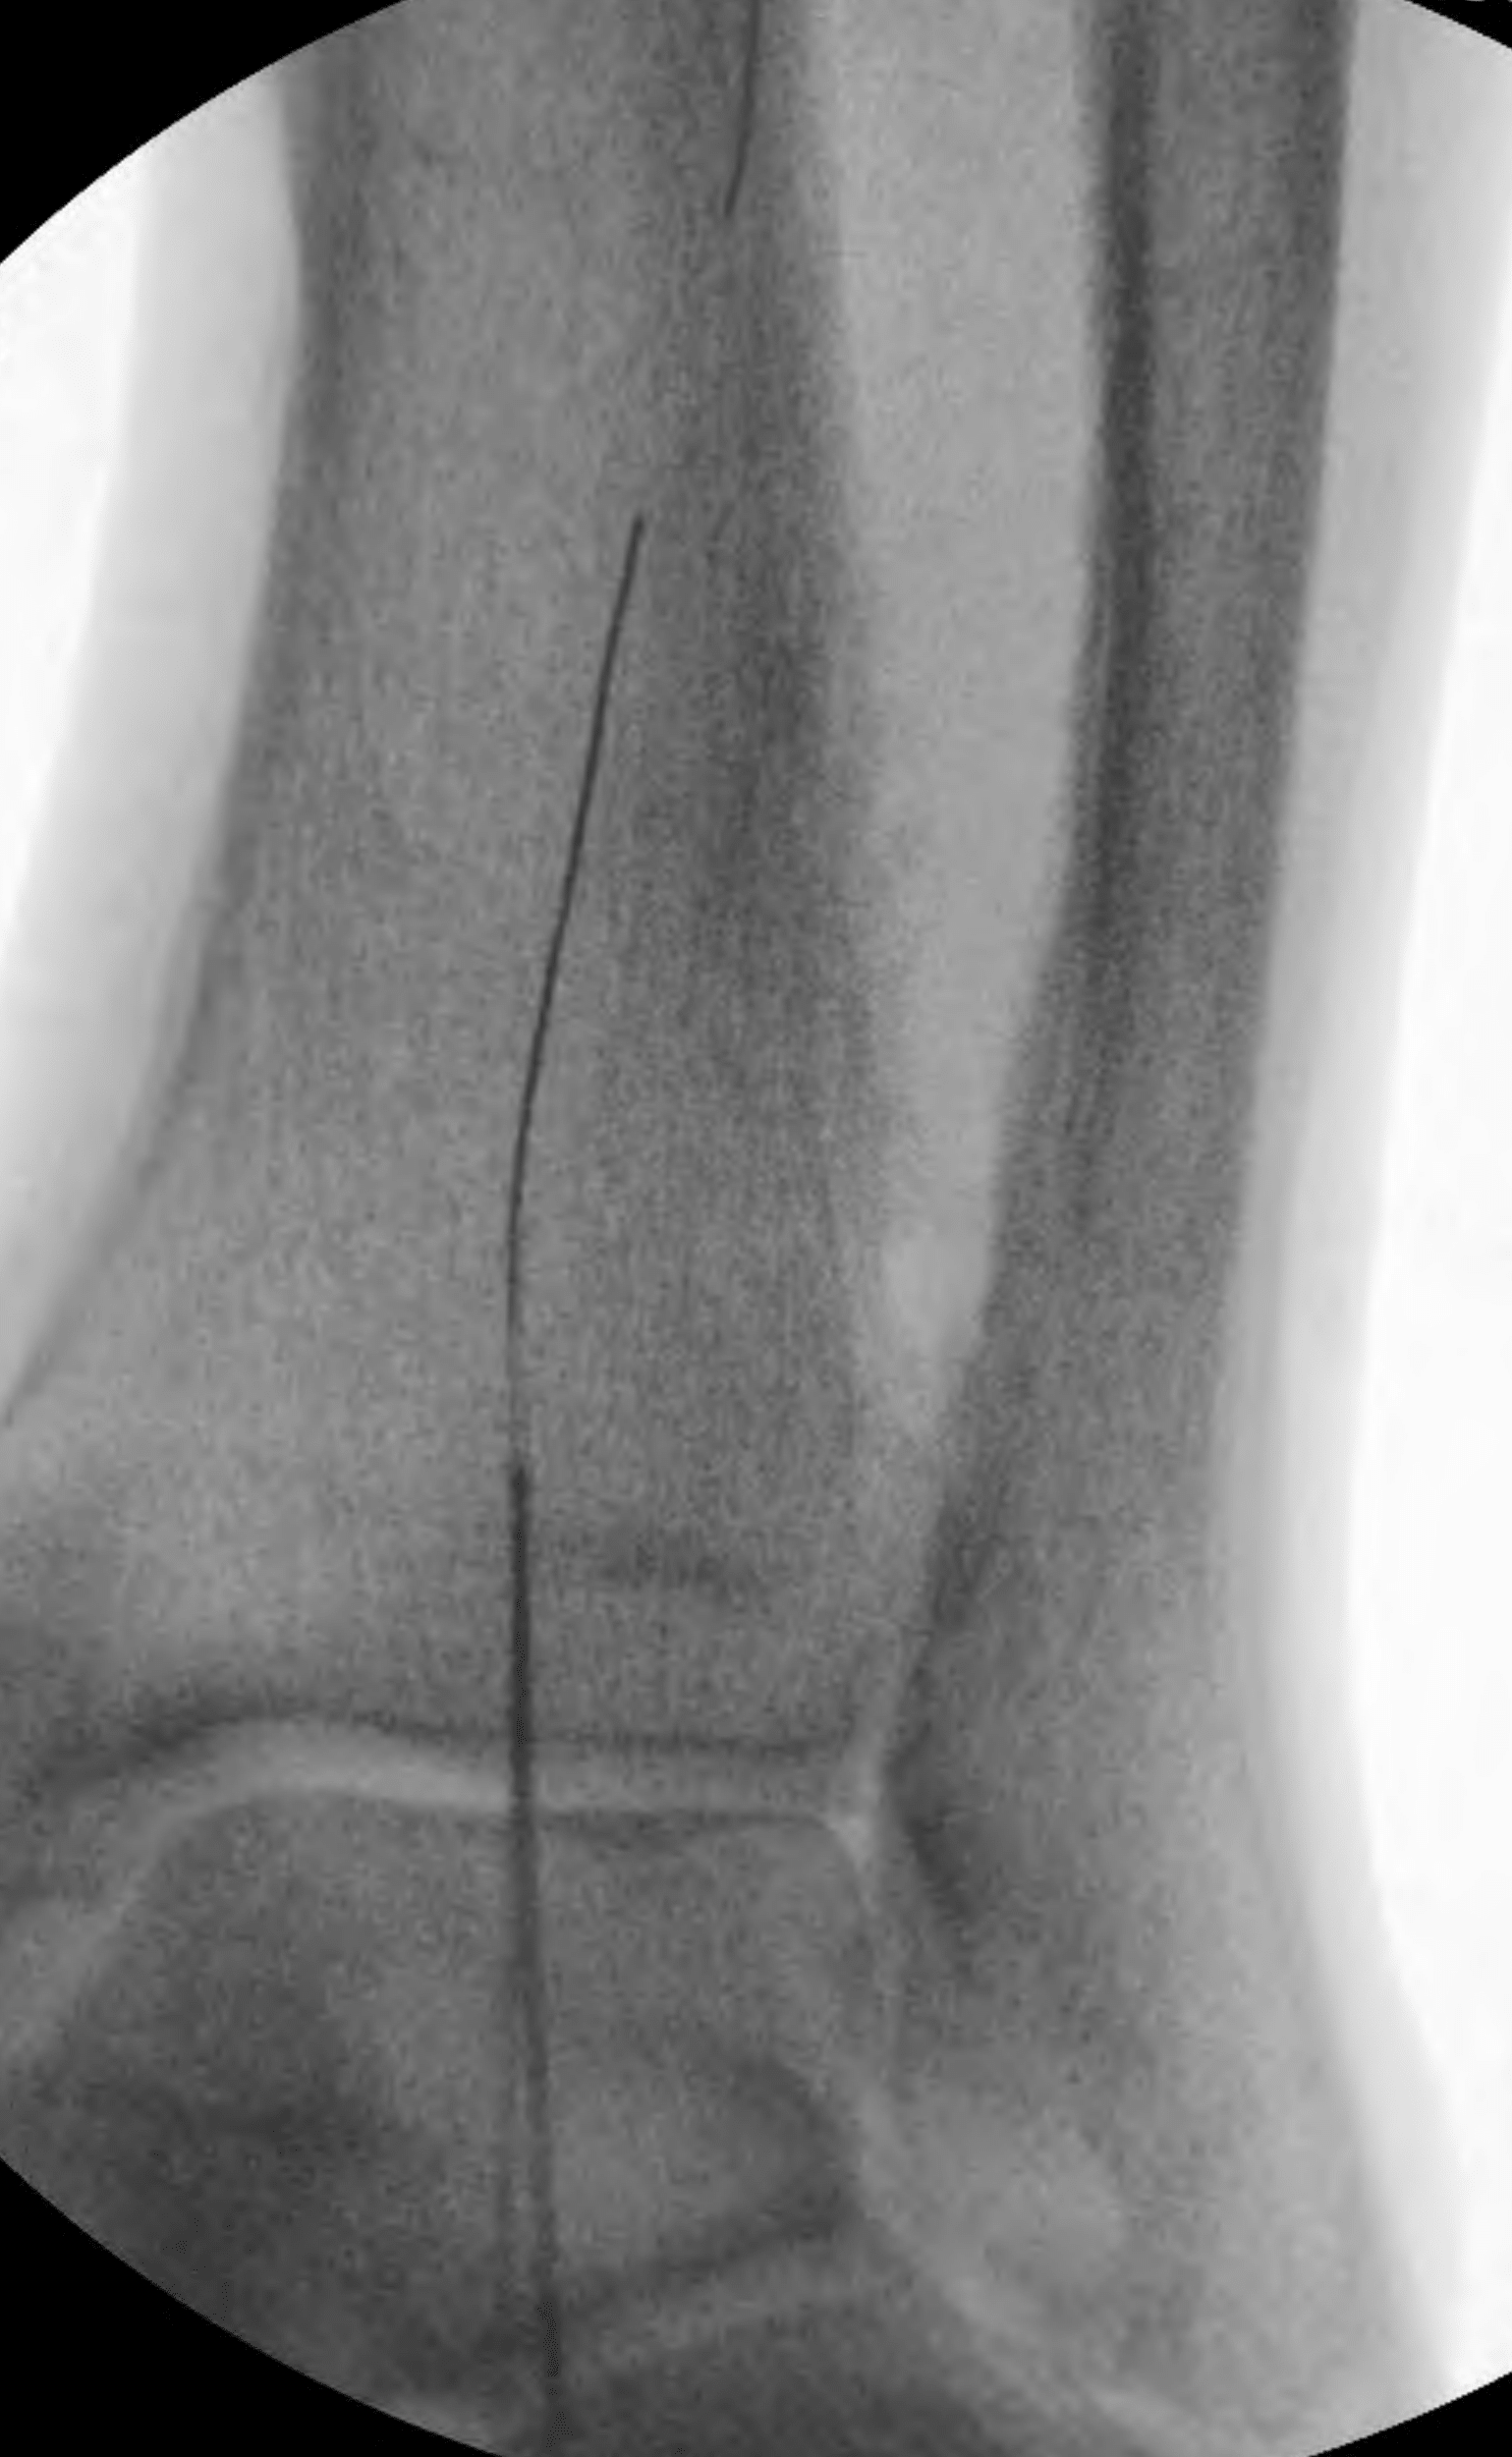

This allowed antegrade advancement of a wire from the “up and over” access into the further distal anterior tibial artery. However, it was still not possible to advance a catheter in antegrade fashion into the true lumen dorsalis pedis artery. Therefore, another retrograde access was obtained—this time, into the patent reconstituted dorsalis pedis artery (Figure 8).

The wire from this new access point was successfully advanced in retrograde fashion through the occlusion in the far distal anterior tibial artery into the more proximal true lumen of the anterior tibial artery. A 2-mm balloon was inserted “bareback” through this new access point, and angioplasty was performed across the far distal anterior tibial artery occlusion (Figure 9). The balloon was withdrawn.